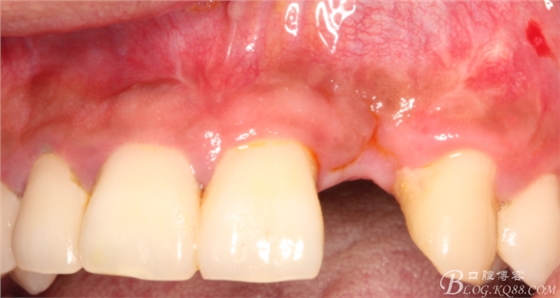

事實(shí)證明,我的做法沒有錯(cuò)誤,一個(gè)月后,軟組織健康愈合。鄰牙軟組織沒有退縮。

再次翻瓣。

先行粘骨膜減張,取自體血液。